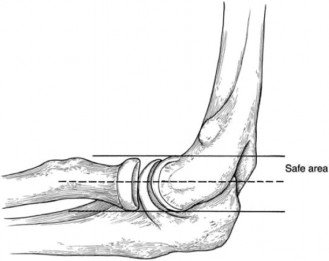

The correct answer is (B). Surgical management of lateral epicondylitis is recommended when pain and dysfunction persist after 6 to 12 months of conservative treatment. The extensor carpi radialis brevis may be released open, percutaneously, or arthroscopically. Specific open debridement techniques vary but generally involve a 2 to 3 cm incision centered distal to the lateral epicondyle. Using sharp dissection, the degenerative tissue within the extensor carpi radialis brevis is debrided, the underlying bone is decorticated, and the tendon is reattached to the bone. With excessive debridement, the lateral ulnar collateral ligament may be

compromised resulting in iatrogenic posterolateral rotatory instability. Keeping debridement anterior to the equator of the radial head prevents destabilization of the elbow (Fig. 2–126).

Figure 2–126_Safe zone for debridement to avoid the lateral ulnar collateral ligament. (Reproduced with permission from Calfee RP, Patel A, DaSilva MF, Akelman E. Management of lateral epicondylitis: current concepts. _J Am Acad Orthop Surg. 2008 Jan;16(1):19–29.)